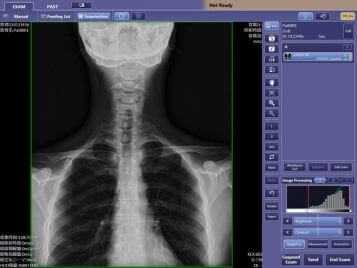

Использование гистограммы в программе для цифровой рентгенографии Image Suite

Гистограмма — это график распределения значений пикселов в снимке.

По оси Х отображается экспозиция от низкой до высокой. По оси Y отображается частота появления. На графике отображается изменение контрастности, например при изменении видов.

При нормальной экспозиции на гистограмме отображается S-образная кривая. Если при обработке изображения возникает ошибка, то на гистограмме отображается прямая диагональная линия, а отображаемый снимок имеет очень низкую контрастность. Это указывает на отсутствие дополнительной обработки изображения на рентгенологическом снимке. Снимок обычно имеет низкую контрастность.

Контрастность снимка можно увеличить с помощью инструментов Яркость/Широта. Перед выполнением настроек убедитесь, что выбран правильный вид. Ошибка обработки снимка может быть вызвана неправильным выбором вида. Если вид правильный, выполните настройки. В режиме "Яркость/Широта" снимок отображается без дополнительной обработки изображения и линия на гистограмме остается прямой диагональной линией.